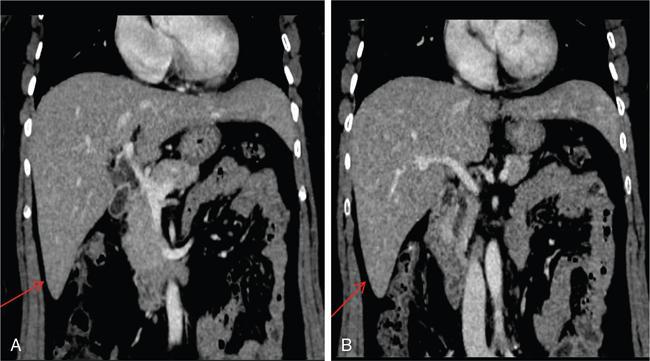

Ritu K. Kashikar, Shrinivas B. Desai Imaging is the mainstay of noninvasive diagnosis of the spectrum of abdominal pathologies or proving absence off thereof. Knowledge of normal anatomy and important normal variants is thus essential for the radiologist in order to avoid misinterpretation or erroneous diagnosis. This chapter highlights the normal anatomy of the hepatobiliary systems including the blood vessel and draining ducts and discusses relevant anatomical variants which may have important clinic implications. The liver is the largest abdominal organ, occupying the right upper abdominal quadrant and is in close approximation with the diaphragm, stomach and the gallbladder. It is largely covered by the costal cartilages. The liver is encapsulated by Glisson’s capsule which is a dense layer of connective tissue. It is covered by peritoneum, except in the regions of gallbladder fossa, fossa for inferior vena cava (IVC), and the bare area. The bare area is the posterocranial aspect of the liver, adjacent to the dorsal body wall, which is not covered by peritoneum. The liver has two surfaces, the convex diaphragmatic surface and a concave visceral surface. The slit in the hepatic hilum is called the porta hepatis and is penetrated by the right and left hepatic ducts (LHDs), hepatic artery and portal vein (PV). The distal portion of the lesser omentum is called the hepatoduodenal ligament and contains the common bile duct (CBD), hepatic artery, PV, nerves of liver and lymphatics. The liver has dual blood supply with hepatic artery providing 25% of hepatic blood and rest by portal vein (Fig. 9.2.1). Five ligaments connect the liver to the undersurface of the diaphragm. These include the falciform, the coronary and two lateral ligaments, all of which are peritoneal folds. The fifth ligament is a fibrous cord-like structure and represents the obliterated umbilical vein. The peritoneum invaginates into the liver parenchyma leading to formation of fissures. There are four normal fissures: fissures for the ligamentum teres, ligamentum venosum and gallbladder and the transverse fissure (Fig. 9.2.2). The liver is organized into microscopic functional units called lobules or acini. A central terminal hepatic venule surrounded by four to six terminal portal triads form a polygonal unit called the hepatic lobule. The terminal portal triad branches line the periphery of the unit. Between the terminal portal triads and the central hepatic venule the hepatocytes are arranged in one cell thick plates, surrounded by sinusoids. The blood flows from the terminal portal triad through sinusoids into terminal hepatic venule. Bile formed within the hepatocytes empties into terminal canaliculi which coalesce into the bile ducts (Fig. 9.2.3). This structure of the functional hepatic unit forms the basis of various functions of the liver. The normal relations of the liver are: The liver can be divided into right, left and caudate lobes. The right and left lobes are separated by the interlobular fissure and is oriented along a line passing through the gallbladder fossa inferiorly and the middle hepatic vein (MHV) superiorly (Fig. 9.2.4). This plane runs from the left of the IVC to the left of the gallbladder fossa and is a called the Cantlie’s line. Use of standardized, segmental anatomy is imperative because it facilitates communication and treatment planning. The segmental anatomy of liver is primarily based on vascular anatomy. The right lobe is divided into anterior and posterior sectors by of the right hepatic vein (RHV). The left lobe is divided into medial and lateraI sectors by an oblique plane connecting the left hepatic vein (LHV) and the falciform ligament. The liver is divided into upper and lower segments at the level of main portal vein (MPV) bifurcation (Fig. 9.2.5). Various systems are used in classification of liver anatomy. These are discussed in Table 9.2.1. The Couinaud’s system is the most commonly used and divides eight sections/segments which are discussed in details below (Table 9.2.2). 1. Segment 1 – Caudate lobe Bounded anteriorly and medially by the fissure for ligamentum venosum (Fig. 9.2.6). 2. Segment 2: Superior segment of the left lateral sector/section Bounded medially by falciform ligament and inferiorly by plane of MPV, also known as the posterior lateral sector (Bismuth, FCAT) (Fig. 9.2.7). 3. Segment 3: Inferior segment of left lateral sector/section Bounded medially by the falciform ligament and superiorly by the plane of the MPV bifurcation, also referred to as lateral anterior sector (Bismuth, FCAT) (Fig. 9.2.8). 4. Segment 4: Left medial sector/section Bounded laterally by falciform ligament and medially by Cantlie’s line (Fig. 9.2.9). 5. Segment 5: Inferior segment of the right anterior sector/section Bounded anteriorly by the gallbladder fossa and posteriorly by the plane of the RHV, superiorly bounded by the plane of MPV bifurcation (Fig. 9.2.10). 6. Segment 6: Inferior segment of the right posterior sector/section Bounded anteriorly by plane of the RHP and superiorly by the plane of the MPV bifurcation (Fig. 9.2.11). 7. Segment 7: Superior segment of the right posterior sector/section Bounded anteriorly by the plane of the RHV and inferiorly by the plane of the MPV bifurcation (Fig. 9.2.12). 8. Segment 8: Superior segment of the right anterior sector/section Bounded anteriorly by the plane of the gallbladder fossa and MHV, posteriorly bounded by the plane of the RHV and inferiorly by the plane of the MPV bifurcation (Fig. 9.2.13). Owing to its broad area of contact with the anterior abdominal wall, the liver is an ideal organ for evaluation with sonography. Ultrasound is commonly used for evaluation of size of the liver. On longitudinal scans obtained through the midhepatic line, if the liver measures 13 cm or less, it is normal in 93% of individuals (Fig. 9.2.14). The size of liver in various planes is discussed in chapter on normograms. When the area of contact between the liver and the anterior border of the right kidney, exceeds below two thirds of the kidney, the liver is considered as enlarged. The normal liver is homogeneous with fine echoes and appears evenly bright. The hepatic veins, PV and fissures interrupt the homogeneity of the liver parenchyma (Fig. 9.2.15). The parenchymal echogenicity may vary depending on the equipment, transducer and gain settings and should be judged by comparison with internal references like right renal cortex, body of the pancreas and PV walls. When compared with the adjacent normal right renal cortex the liver normally appears hyperechoic or isoechoic. The pancreas in a young individual is hypoechoic compared to the liver, and isoechoic in middle aged adults. As age progresses and fatty infiltration of the pancreas occurs, the pancreas appears hyperechoic to the liver. The liver is hypoechoic to the spleen. The normal liver reveals a density of 55–65 HU on nonenhanced scan and should appear homogenous with the exception of hypodensity in the regions of vessels and fissures. The liver parenchymal enhancement is minimal the arterial phase, with increase in density by only approximately 10 HU. This phase is usually to access vascular anatomy and to detect neovascular enhancing lesion like HCC, metastasis. Considering the fact that 75% of heptic venous supply is from the PV, the normal hepatic parenchyma shows maximum enhancement in the portal venous phase. During the venous/delayed phase the hepatic attenuation starts falling (Fig. 9.2.16). The hepatic fissures appear as linear fat containing structures. All the four fissures are well identifies on CT (Figs. 9.2.17–9.2.20). Normal liver should demonstrate uniform T1 signal similar or isointense to the paraspinal muscles and slightly hyper intense to the spleen. No signal drop should be seen on in or opposite phase. On T2W1 images liver appears slightly hyperintense to paraspinal muscles, isointense to pancreas and hypointense to spleen (Fig. 9.2.21). Following administration of extracellular contrast agents the normal liver parenchyma enhances on PV phase similar to that seen on CT. The arterial phase is preserved to determining vascular anatomy, variants and tumoural enhancement. Gadoxetic acid (Eovist) and gadobenate dimeglumine (MultiHance) are hepatobiliary agents showing excretion by the liver. In the case of gadoxetic acid, hepatic excretion is ~50%, which allows imaging in the hepatobiliary phase at ~20 minutes following injection. Gadobenate has only 3%–5% biliary excretion with hepatobiliary phase at approximately 40 minutes (Fig. 9.2.22). This property makes these agents useful in detection of nonhepatocyte containing lesions which appear hypointense to background liver on hepatobiliary phase. Hepatic anatomic variants are relatively common and represent normal interindividual variation of liver morphology. Normal Anatomic Variants Anatomic anomalies Accessory and pseudofissures may be seen in the liver. True accessory fissures result from infolding of the peritoneum usually along the undersurface of the liver and are rare. The inferior accessory fissure is the commonest accessory fissure and divides the posterior segment of the right hepatic lobe into lateral and medial portions. Diaphragmatic slips may cause indentation over the liver surface and are not commonly seen on imaging (Fig. 9.2.23). Leftward extension of the lateral segment of the left hepatic lobe appearing as a crescentic density that wraps around the spleen is referred to as sliver of liver. The left lobe of the liver may exhibit various forms: leaf like; spatular; truncated pyramid/wedge shaped; and a bifid appearance (Fig. 9.2.24). Elongated left lobe may be mimic splenomegaly, perisplenic hypoechoic collections or less commonly tumours. Imaging clues to diagnosis are establishing contiguity with liver and visualization of parenchymal vessels coursing through. The portion of the liver that extends medially from the right lobe between the IVC and fissure for ligamentum venosum is called the caudate lobe. The caudate lobe is divided inferiorly into a lateral caudate process and a medial papillary process. The medial papillary process projects medially towards the pancreatic head and has applied importance (Fig. 9.2.25). Riedel’s lobe is a tongue-like projection from the anterior aspect of the right lobe and the most common accessory lobe of the liver. It is seen most frequently in asthenic women. The reported prevalence of RL, ranges from 3.3% to 14.5% and the prevalence is higher in women than in men. It can be 20 cm or more in length and may extend up to the iliac fossa. It is usually asymptomatic and is discovered incidentally (Fig. 9.2.26). Accessory liver lobes are defined as a supernumerary lobe of normal hepatic parenchyma in continuity with the liver. This is a rare entity and usually occurs as a result of congenital ectopic hepatic tissue, although rarely may occur as a result of trauma or surgery. Various systems are proposed for classification of ALL. Another method of classification has been proposed based on biliary drainage and presence or absence of capsule. Accessory lobes can be readily diagnosed and characterized on CT or magnetic resonance imaging (MRI) done for related or unrelated conditions. CT shows the lesion as a soft–tissue density mass attached to the liver and isodense to the organ. The portal/hepatic venous branches can be seen coursing through it, in contiguity with the liver (Fig. 9.2.27). The coeliac axis trifurcates into common hepatic, splenic and left gastric arteries at the level of T12–L1. The common hepatic artery becomes the proper hepatic artery after origin of the gastro-duodenal artery. The hepatic artery proper ascends anterior to the PV and medial to the CBD and divides in to right and left hepatic artery (LHA). Occasionally the middle hepatic (segment 4) artery arises from hepatic artery proper. The hepatic artery appears as a tubular hypoechoic structure and shows antegrade flow on Doppler (Fig. 9.2.28). Normally the resistive index is low ranging between 0.55 and 0.7. The hepatic artery, its anatomy, branches, course, calibre are best evaluated on arterial phase of dynamic CT (Fig. 9.2.29). This is also the preferred modality prior to hepatobiliary surgical planning. Contrast-enhanced MRI also shows the above details but spatial resolution is lower. Road map of the arterial vascularity of the donor and recipient is a prerequisite for transplant surgery and complex hepatobiliary surgery. Detailed hepatic arterial anatomy and its variations have its significance in liver surgeries and interventional hepatic procedures, relative to the hepatic lobe involved. A classification method was described by Michel et al. in 1955, and is discussed in Table 9.2.3 (Fig. 9.2.30). I: standard anatomy ~60% (range 55%–61%) II: replaced LHA ∼7.5% (range 3%–10%) III: replaced RHA ~10% (range 8%–11 %) IV: replaced RHA and LHA ~1% V: accessory LHA from LGA ~10% (range 8%–11%) VI: accessory RHA from SMA ~5% (range 1.5%–7%) VII: accessory RHA and LHA ~1% VIII: accessory RHA and LHA and replaced LHA or RHA ~2.5% IX: CHA replaced to SMA ~3% (range 2%–4.5%) X: CHA replaced to LGA ~0.5% Other unclassified variants are: The two most common variants are the replaced right hepatic artery (RHA) arising from the SMA (Fig. 9.2.31) and replaced LHA arising from the left gastric artery (Figs. 9.2.32–9.2.34). Segment 4 artery – Middle hepatic artery (MHA) The middle hepatic artery usually arises from the LHA, it may, however, arise from the RHA (Fig. 9.2.35). The knowledge regarding origin of MHA is imperative in transplant surgery. The MHA can arise from RHA in Patients with replaced LHA. In patients with replaced RHA, the MHA arises from LHA (Fig. 9.2.36). Because of the considerable variability of hepatic arterial anatomy, assessment of this anatomy is crucial in the preoperative evaluation of potential living liver donors. Relevance of donor and recipient arterial anatomy is discussed in details in chapter on liver transplant. The relationship between the arterial variant and tumour is important to establish prior to major surgeries. Injuries to aberrant hepatic vessels and secondary ischaemic biliary strictures can be avoided. A replaced RHA has a more posterior course and long length. This variant may be advantageous in patients undergoing right lobar resection. However, there is greater propensity of involvement of replaced RHA by pancreatic head. The radiologist must be vigilant in reporting this variant (Fig. 9.2.37). Accessory RHA can, however, be sacrificed even if encased by neoplasm. An accessory LHA needs to be ligated separately in surgeries where blood supply in the porta hepatis is occluded. Replaced LHA from LGA maybe injured in case of surgeries at the level of hiatus. Hence this variant should be informed to surgeon in patients undergoing gastric surgeries. Preoperative mapping of the hepatic arterial anatomy prior to placement of intraarterial chemotherapy pumps is essential because it helps in deciding whether the candidate is suitable for the procedure and also if technical modifications are needed. The intraarterial infusion pump should be placed in the dominant hepatic artery as proximal as possible, but beyond GDA origin. Inpatients with standard anatomy, the pump is usually placed in the hepatic artery prior just after GDA origin. The location of pump can be modified in patients with variant anatomy, based on origin of GDA and dominant hepatic vessel. The PV is the main vessel in the portal venous system and drains blood from the gastrointestinal tract and spleen to the liver.